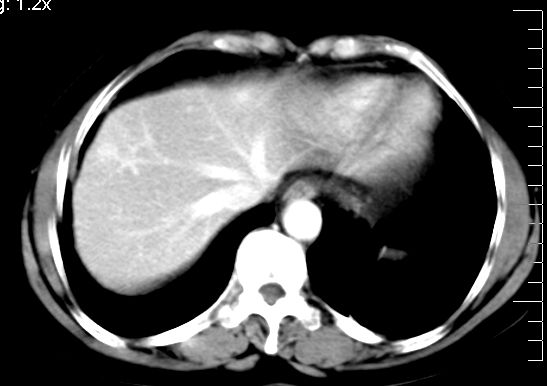

肝大小形态未见异常,肝内外胆管无扩张,肝s8段见一动脉期明显血管样强化结节,门脉期呈高密度,延迟期呈等密度,胆囊不大,增强扫描见胆囊及胆囊颈管壁增厚,有强化。

2、肝s8段结节,考虑小血管瘤。

肝右上叶血管瘤!

考虑肝右叶前上段包膜下小血管瘤。

5.增强,脾特别明显是怎么回事?